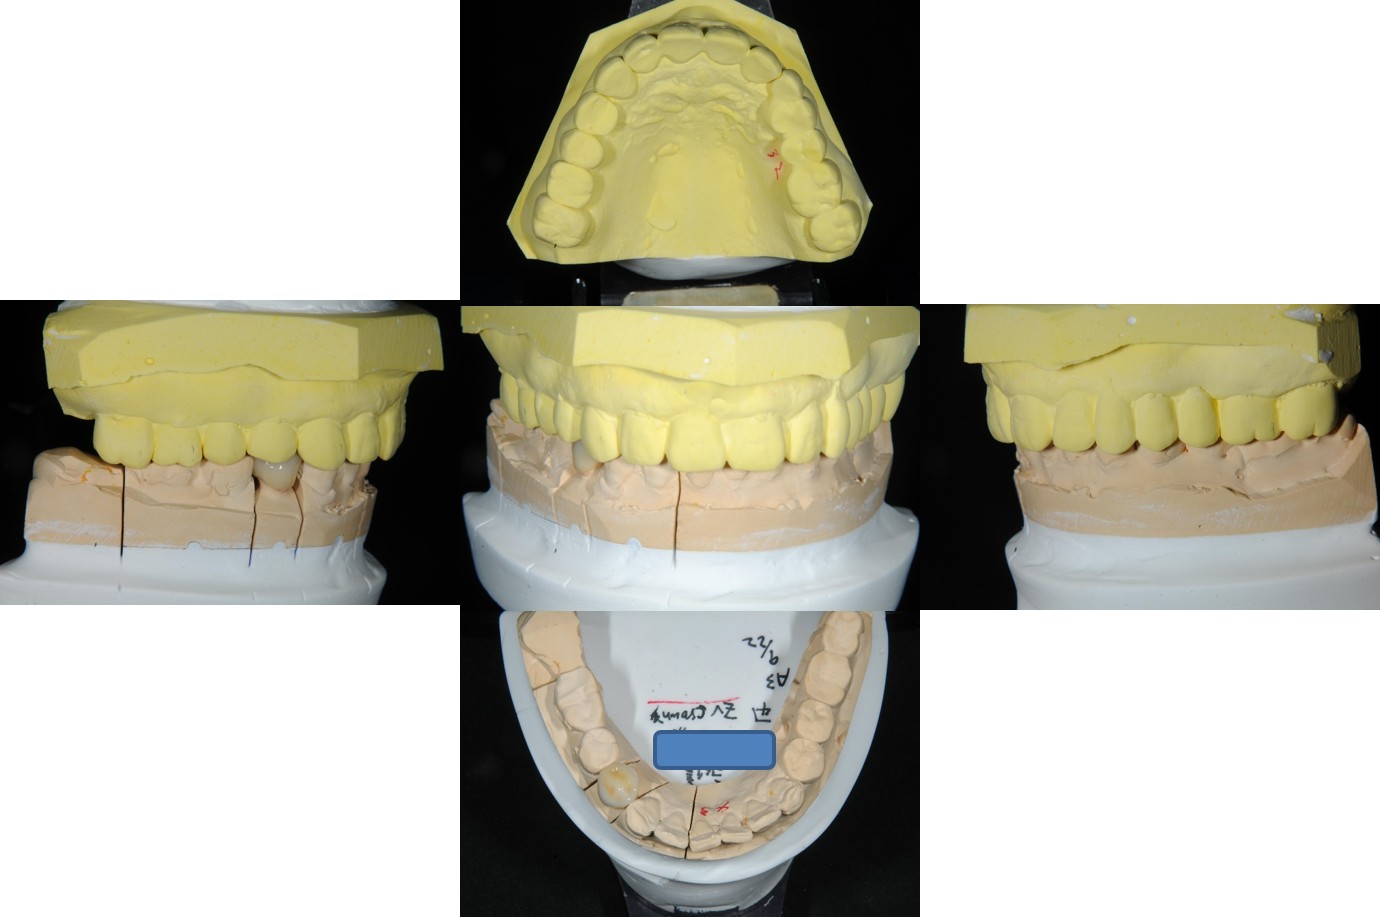

面弓取得,上咬合器

技師於咬合器上製作假牙